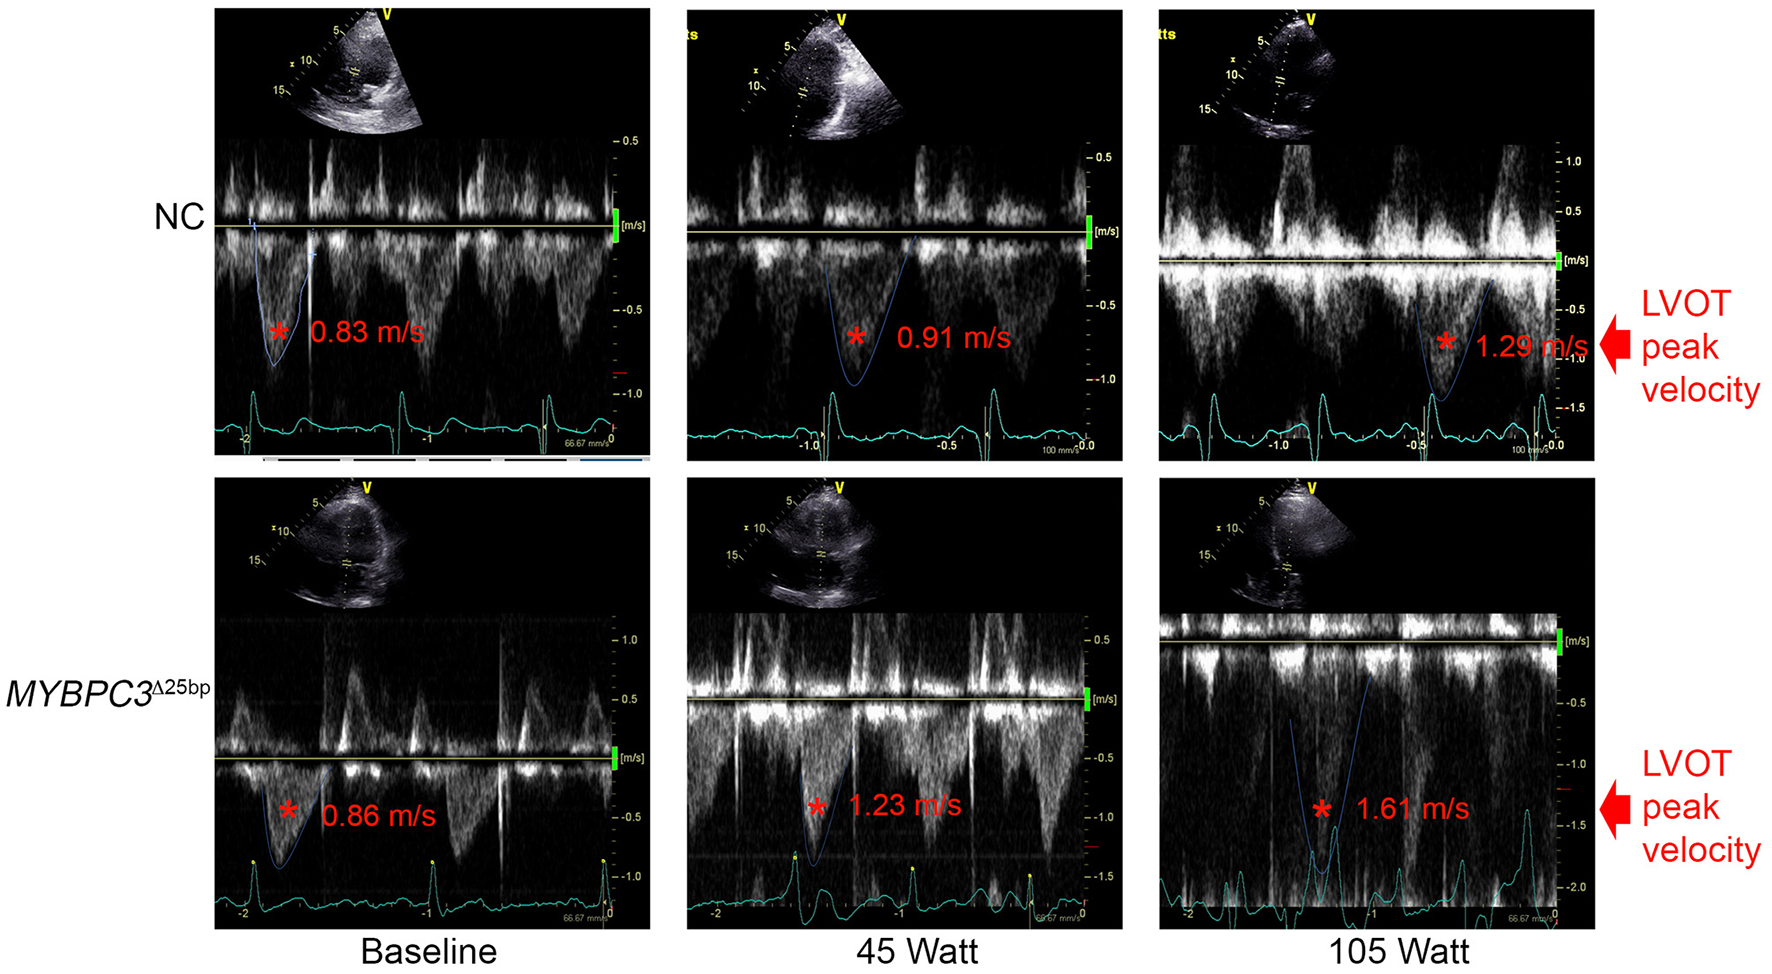

Figure 3

Spectral Doppler data depict LVOT peak velocity. Representative apical five-chamber view at baseline, 45 (W), and 105 (W) in a NC (upper panel) subject and a MYBPC3Δ25bp variant carrier (lower panel). NC, non-carriers.

While baseline echocardiography parameters were not different between the two groups (MYBPC3Δ25bp carriers and NCs) (Table 1), significant differences came to light under exercise stress condition in the following parameters: LV end-diastolic diameter (LVIDdia), LVEF, LVOT and AV peak velocities (pv), and the ratio of early to late ventricular filling velocity (E/A ratio) (Table 2, Figures 3, 4). Stress-induced LVIDdia augmented in NCs, while it did not increase in MYBPC3Δ25bp carriers with a significant difference between the two groups (CI: 0.239 ± 0.125; p = 0.0002), indicative of impaired relaxation and diastolic impairment. Strikingly, the estimated effect of exercise stress and genotype showed that MYBPC3Δ25bp carriers had significantly higher LVEF (%) (CI: 4.57 ± 1.93; p < 0.0001), higher LVOT pv (m/s) (CI: 0.197 ± 0.069; p < 0.0001), and higher AV pv (m/s) (CI: 0.103 ± 0.081; p = 0.01) in comparison to NCs. This was consistent with the findings that stress-induced LVIDdia increase was significantly muted in carriers during exercise, as compared to NCs (CI: 0.239 ± 0.125; p = 0.0002). Further, E/A ratio, a marker of ventricular diastolic compliance, was significantly lower in carriers as compared to NCs (CI: 0.107 ± 0.102; p = 0.038) and the ratio of early transmitral peak velocity flow to early diastolic mitral annulus velocity (E/e' ratio), which showed a non-significant difference between the groups (CI: 0.738 ± 0.795; p = 0.068). Although stress-induced right ventricular systolic excursion velocity (s') was increased similarly in both groups, tricuspid annular plane systolic excursion (cm) increased more in carriers (slope: 0.008; p = 0.0001) from the baseline, consistent with right ventricle functional differences. These findings are indicative of LV hypercontractility among asymptomatic carriers of the MYBPC3Δ25bp variant under exercise stress conditions and evidence of diastolic impaired relaxation at high workloads, suggesting that MYBPC3Δ25bp is an independent risk allele with subclinical pathology prior to late-onset LV dysfunction (16, 22) in the US SA population.